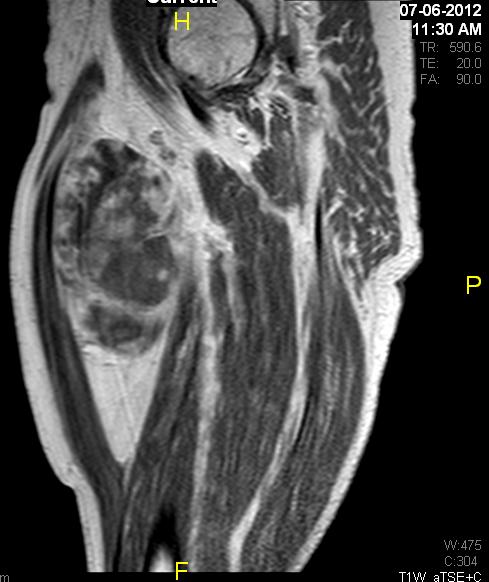

• Large encapsulated lipomatous mass with multiple thick internal trabeculations. (Fig. 1 – 13)

• Signal loss on FS T1 weighted images, and focal nodules(>1 cm is suggestive of a DDLS). (Fig. 1 & 7)

• Contrasted images show hyper-enhancement of the tumors. (Fig. 4, 5, 11-13)

Fig. 11 – 13 Axial (Fig. 11), Coronal (Fig. 12) and Sagital (Fig. 13) contrasted T1-weighted MR images show a large heterogeneous mass with central and peripheral

enhancement. Multiple thick trabeculations. Central low signal intensity image is compatible with necrosis and hemorrhage.